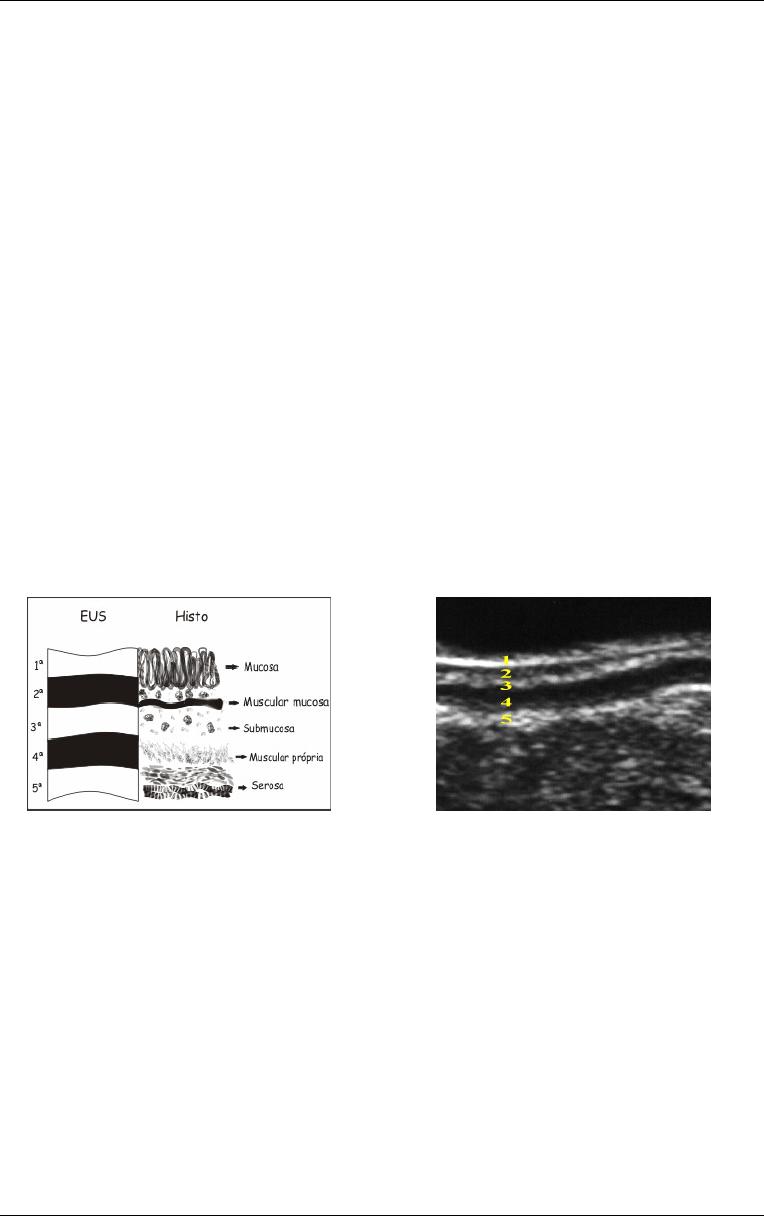

Figura 11

Imagem esquemática da relação das camadas

ecográficas com a histologia. Obs. Imagens cedidas pelo Dr.

Lucio Rossini.

Figura

16

-

Representação das diferentes

penetrações de nódulos de endometriose na

parede intestinal (imagens ovaladas

numeradas de 1 a 5), seguindo os critérios da

Classificação Echo-logic. T- indica que a lesão

está sendo classificada segundo a

profundidade do nódulo de endometriose na

parede intestinal. EUS = ecoendoscopia,

HISTO = histologia, 1 = nódulo de

endometriose extra-intestinal, 2 = nódulo de

endometriose invadindo a serosa intestinal, 3 =

nódulo de endometriose invadindo a muscular

própria, dividida em 3a= espessura menor que

5mm e 3b= espessura maior que 5mm, 4 =

nódulo de endometriose invadindo a

submucosa, 5 = nódulo de endometriose

invadindo a camada mucosa. Obs. Imagem

cedida pelo Dr. Lucio Rossini.